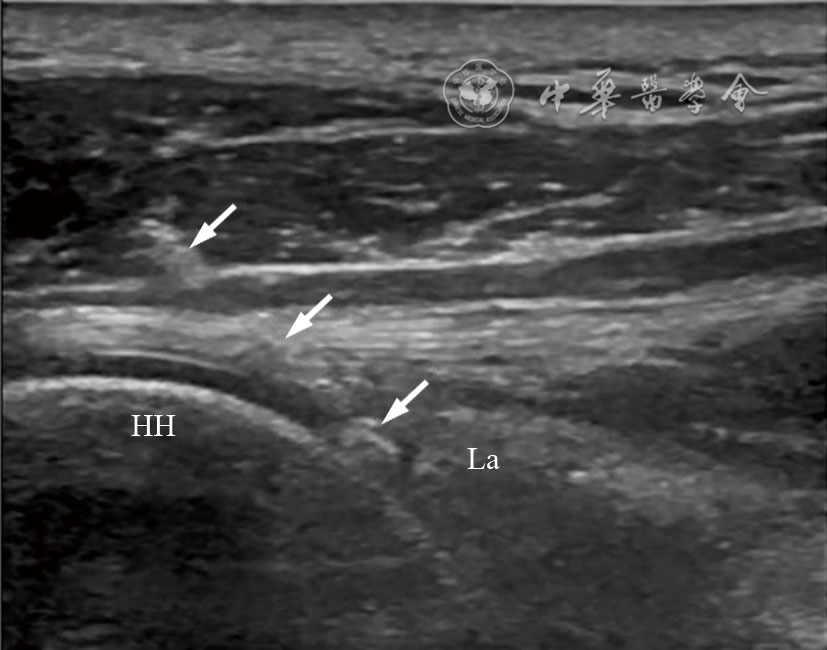

图1 超声引导肩后部肩关节腔注射治疗图像 注:HH为肱骨头;La为盂唇;箭头所示为穿刺针